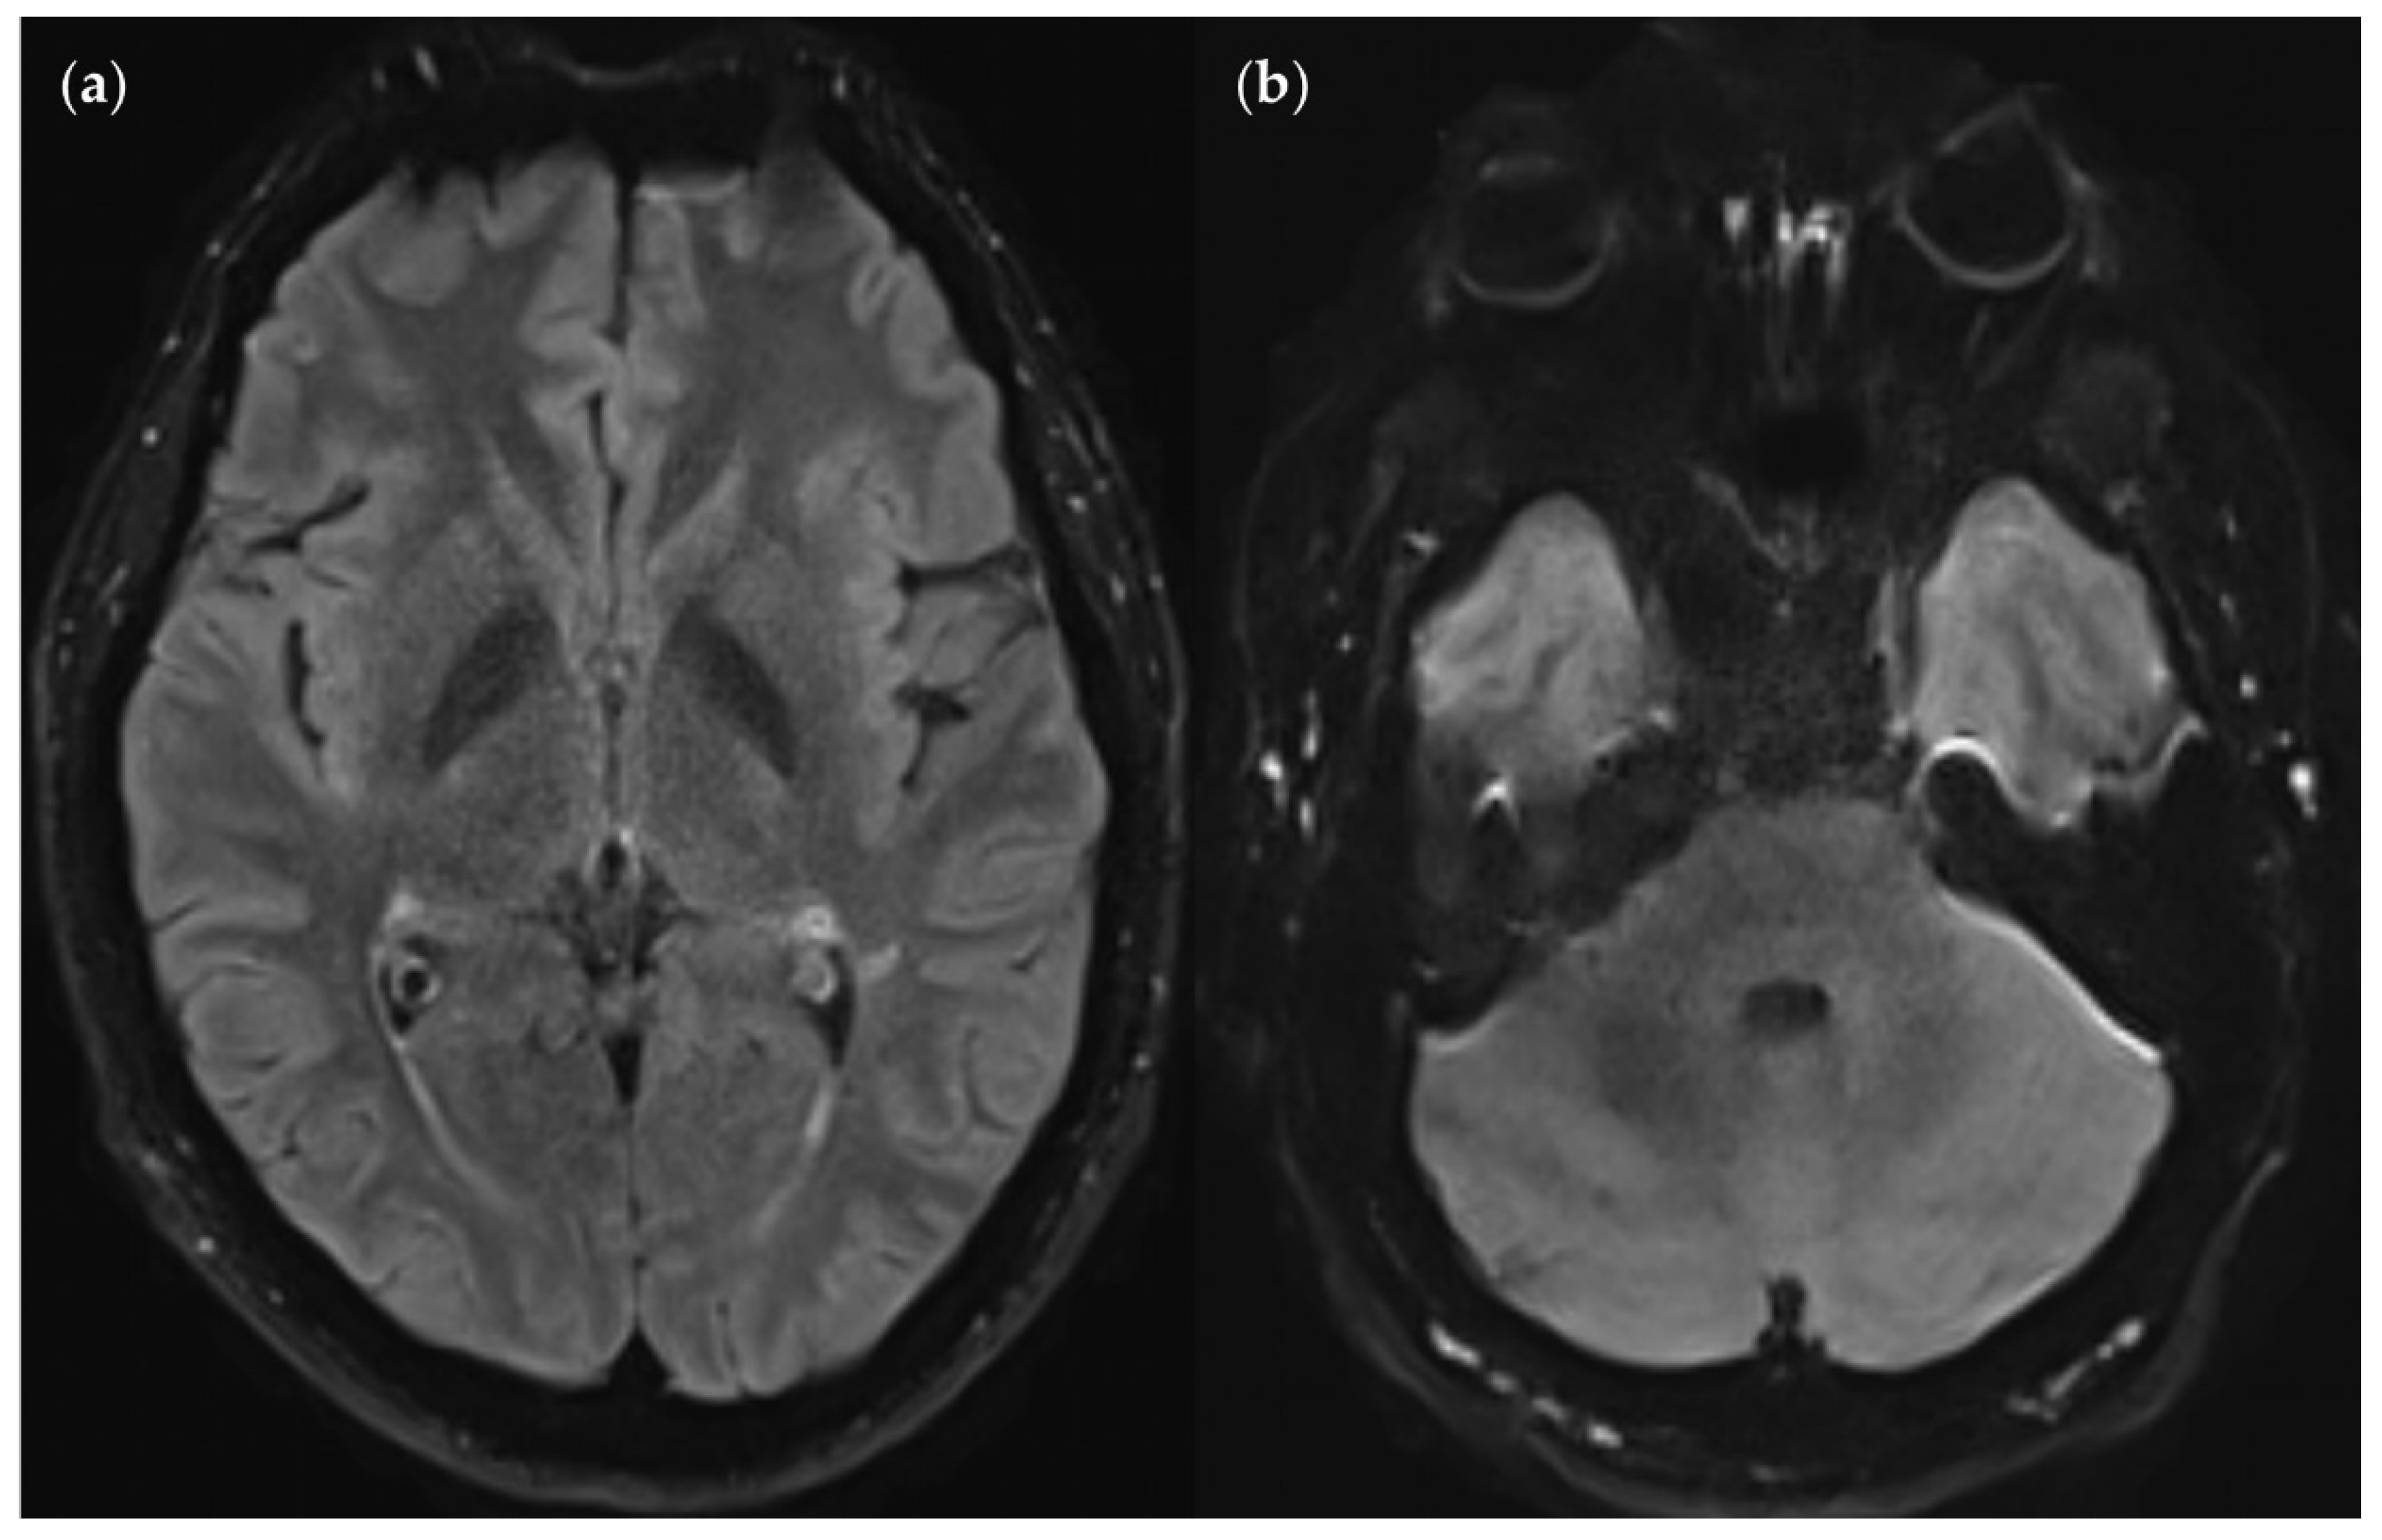

SNR and CNR in FLAIRUF images (top) and FLAIR3Da images (bottom). (a) Inflammatory lesions. Continuous arrow: Large lesion in the right mesencephalon (approx. 8 mm × 6 mm). The SNR appeared reduced in the center of the FLAIRUF image, thus decreasing the lesion conspicuity. Dotted arrows: Temporal lesions (right: approx. 5 mm × 4 mm; left: approx. 4mm × 3 mm). The SNR appeared significantly improved in posterior brain regions in the FLAIRUF images, thus equaling lesion conspicuity between the image variants. Note that in FLAIR3Da, the left lesion was better visible in the adjacent image slice (not depicted). Arrowhead: Partially imaged, right temporal lesion (approx. 3 mm × 1 mm in the slice image depicted). Comparison of adjacent slice images showed equal lesion conspicuity. (b) Arrow: Left frontal lesion (approx. 2 mm × 1 mm). Excellent lesion conspicuity in the FLAIRUF image due to very good SNR and CNR. (c) Infratentorial lesions. Continuous arrow: Large lesion (approx. 9 mm × 6 mm) that was not visible in the FLAIRUF image owing to low SNR and CNR. Dotted arrow: Large lesion (approx. 8 mm × 6 mm) that was less visible in the FLAIRUF image due to reduced SNR and CNR. Arrowhead: Large lesion (approx. 3 mm × 2 mm) that was better visible in the FLAIRUF image. Note that the SNR improves towards the outer regions of the FLAIRUF image.

Figure 13.